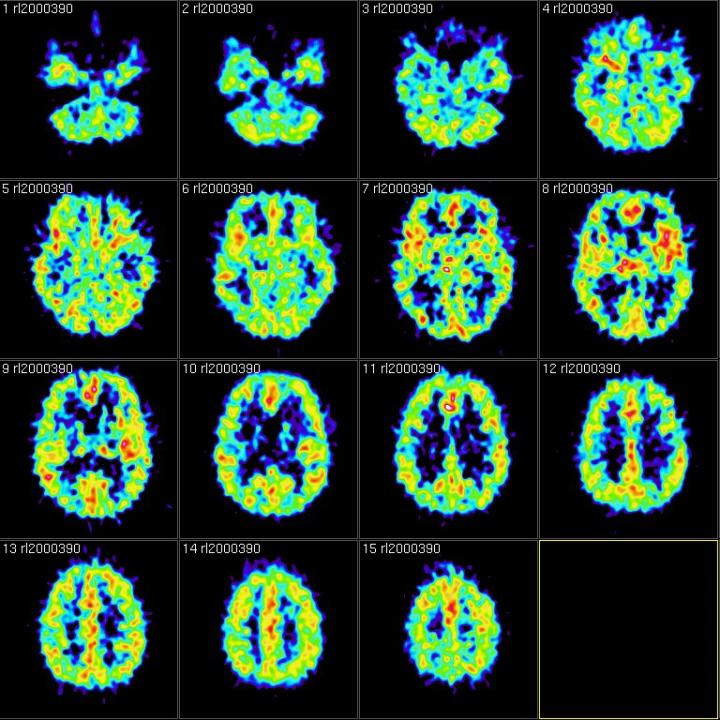

Since Ancient Greece, memory theorists have known that we use context — or the situation we’re in, including sights, sounds, smells, where we are, who we are with — to organize and retrieve our memories. But the Dartmouth- and Princeton-led team wanted to know whether and how people can intentionally forget past experiences. They designed a functional magnetic resonance imaging (fMRI) experiment to specifically track thoughts related to memories’ contexts, and put a new twist on a centuries-old psychological research technique of having subjects memorize and recall a list of unrelated words. In the new study, researchers showed participants images of outdoor scenes, such as forests, mountains and beaches, as they studied two lists of random words, manipulating whether they were told to forget or remember the first list prior to studying the second list.

“Our hope was the scene images would bias the background, or contextual, thoughts that people had as they studied the words to include scene-related thoughts,” says lead author Jeremy Manning, an assistant professor of psychological and brain sciences at Dartmouth. “We used fMRI to track how much people were thinking of scene-related things at each moment during our experiment. That allowed us to track, on a moment-by-moment basis, how those scene or context representations faded in and out of people’s thoughts over time.”

The study’s participants were told to either forget or remember the random words presented to them interspersed between scene images. Right after they were told to forget, the fMRI showed that they “flushed out” the scene-related activity from their brains.

“It’s like intentionally pushing thoughts of your grandmother’s cooking out of your mind if you don’t want to think about your grandmother at that moment,” Manning says. “We were able to physically measure and quantify that process using brain data.”

But when the researchers told participants to remember the studied list rather than forget it, this flushing out of scene-related thoughts didn’t occur. Further, the amount that people flushed out scene-related thoughts predicted how many of the studied words they would later remember, which shows the process is effective at facilitating forgetting.

The second implication is more subtle but also important. “It’s very difficult to specifically identify the neural representations of contextual information,” Manning says. “If you consider the context you experience something in, we’re really referring to the enormously complex, seemingly random thoughts you had during that experience. Those thoughts are presumably idiosyncratic to you as an individual, and they’re also potentially unique to that specific moment. So, tracking the neural representations of these things is extremely challenging because we only ever have one measurement of a particular context. Therefore, you can’t directly train a computer to recognize what context ‘looks like’ in the brain because context is a continually moving and evolving target. In our study, we sidestepped this issue using a novel experimental manipulation — we biased people to incorporate those scene images into the thoughts they had when they studied new words. Since those scenes were common across people and over time, we were able to use fMRI to track the associated mental representations from moment to moment.”